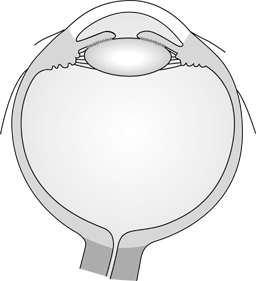

The uveal tract consists of the choroid, ciliary body, and iris (Figure 7-1). Uveal tumors and inflammations (uveitis) together comprise the vast majority of diseases affecting these structures. Many neoplastic and inflammatory disorders of the uveal tract are associated with systemic diseases, some of which can be life-threatening if unrecognized. The anterior uveal tract is best examined with a slitlamp, though gross inspection can be performed with a flashlight and loupe. Examination of the posterior uveal tract requires the use of either a direct or indirect ophthalmoscope or a slitlamp.

Figure 7-1

Figure 7-1: The uveal tract consists of the iris, the ciliary body, and the choroid.